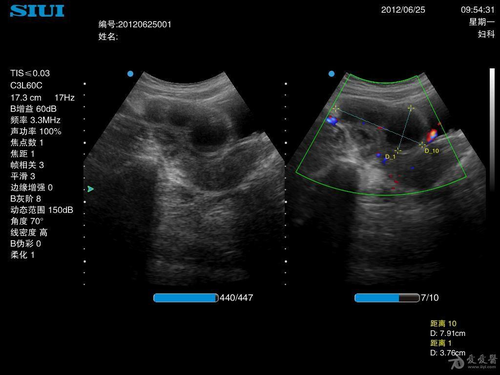

3、输卵管出现积水。当女性的输卵管出现积水以后,通常会感到下腹隐隐作痛。

右侧的输卵管疼痛极有可能是炎症所致,建议立即去往医院接受检查,在日常生活中可以使用热水袋进行局部热敷,以免着凉,在经期间也要注意饮食情况,注意均衡饮食,饮食以清淡为主,营养为主。如果右边输卵管隐隐作痛,则也有可能是输卵管内有结石,需要及时去往医院取出,慢慢恢复身体。